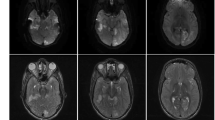

The electromyography of limbs showed decreased electrical activity in response to the muscle stimulation, suggestive of neurogenic changes. Brain magnetic resonance imaging (MRI) showed bilateral T2 hyperintensities of the globus pallidus, and lesions in periventricular tissue and left subfrontal cortex (Fig. 1). For evaluation of intelligence quotient, the patient scored 85 points by Wechsler Preschool and Primary Scale of Intelligence (Fourth Edition) (WPPSI-IV). In terms of assessment for exercise tolerance and endurance, the 6-minute walking distance (6MWD) was 216 m, compared with a reference value of 494 m for healthy boys at the same age. The genomic sequencing confirmed a hemizygote mutation: NM_000284.3 (PDHA1): c.214 C> T, p.R72C. This variant was determined to be pathogenic according to ACMG Guidelines, 1993 [PMID: 8504309] [7]. The accession number is RCV000011627.8 from the ClinVar database [8]. Combined with the results of genetic testing, a comprehensive diagnostic workup confirmed the diagnosis of PDC deficiency.